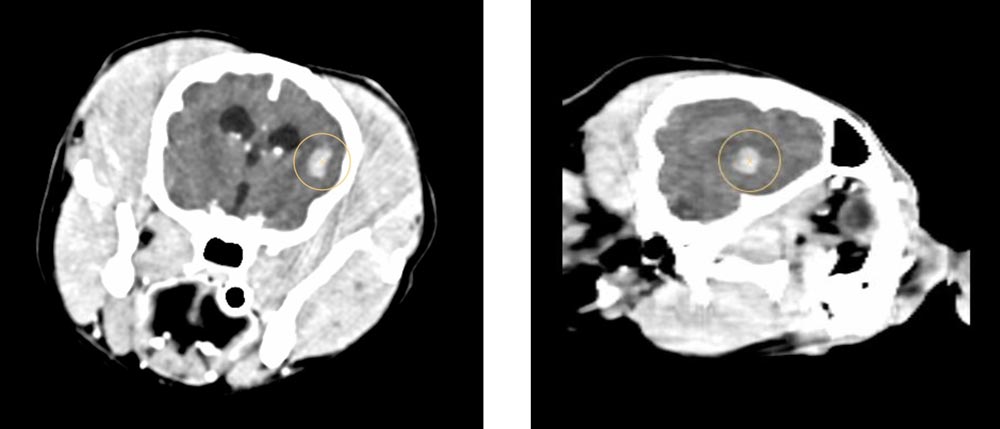

Dank des CTs können wir detaillierte 3D-Bilder von Organen und Geweben erstellen und so Erkrankungen erkennen, die mit herkömmlichen Methoden schwer sichtbar wären. Dies ist besonders hilfreich bei der Diagnose von Tumoren, Verletzungen oder Erkrankungen der inneren Organe und des Nervensystems.